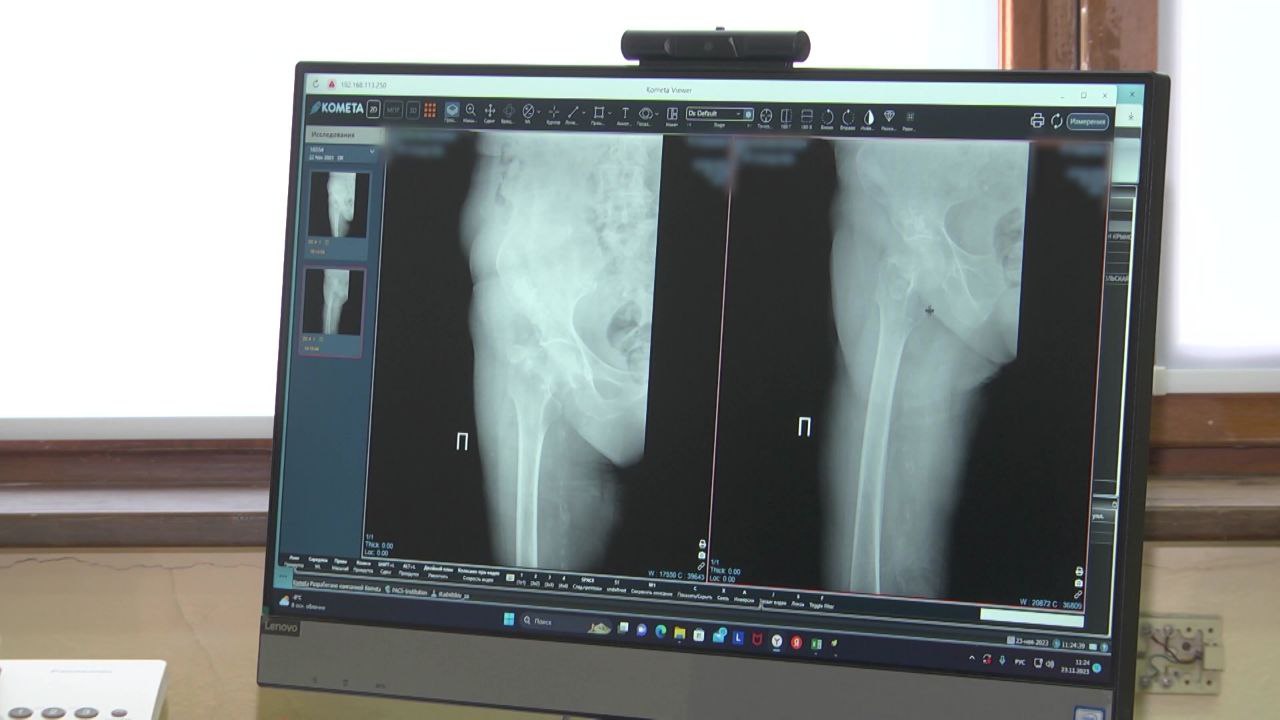

Вячеслав Гладков инициировал опрос среди пациентов, ожидающих операции по эндопротезированию

«Вчера на заседании правительства Белгородской области министр здравоохранения Андрей Иконников отчитался о ходе реализации программы по эндопротезированию коленных и тазобедренных суставов. Это проект, который состоялся – начали его реализацию- из-за огромного количества жалоб, которые поступали в течение нескольких лет, на то, что ожидание на данную операцию составляло до трех лет, и за этот период времени уже происходили существенные негативные изменения в организме, которые уже через 3 года не позволяли помочь человеку, которому требовалась операция», – рассказал губернатор.

Напомним, в этом году в регионе проведут около четырёх тысяч операций.